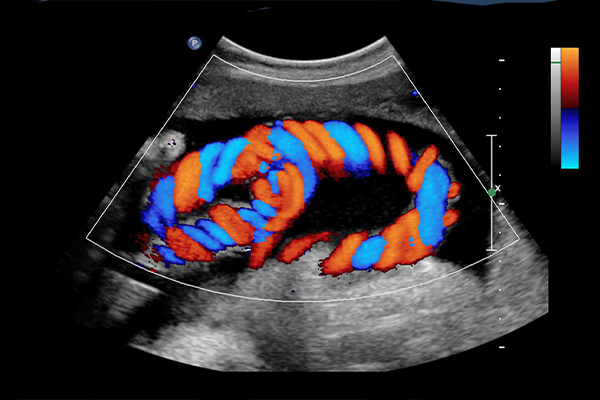

Colour Doppler

₹1200 onwards- Doppler Lower Limb Veins Single

- Doppler Obstetric

- Doppler Carotid and Vertebral

- Doppler Lower Limb Arteries Single

- Doppler Varicocele

- Doppler Renal Arteries

- Doppler Anomaly 4D

- Doppler Twins 3rd Trimester

- Doppler Upper Limb Arteries Both

- Doppler Renal Arteries + Abdomen Pelvis

- Doppler Lower Limb Arteries + Veins Both

- Doppler Others